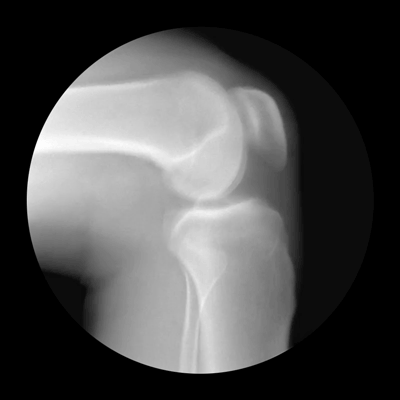

Cameron Drake ze San Francisca vytvořil ve spolupráci s ortopedem Noahem Weissem sérií gifů, které zachycují pohyb kloubů přes rentgenové záření. Výsledek je ohromující.